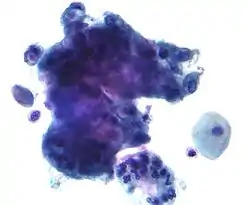

Endocervical adenocarcinoma on a pap test.

Candida organisms on a pap test.